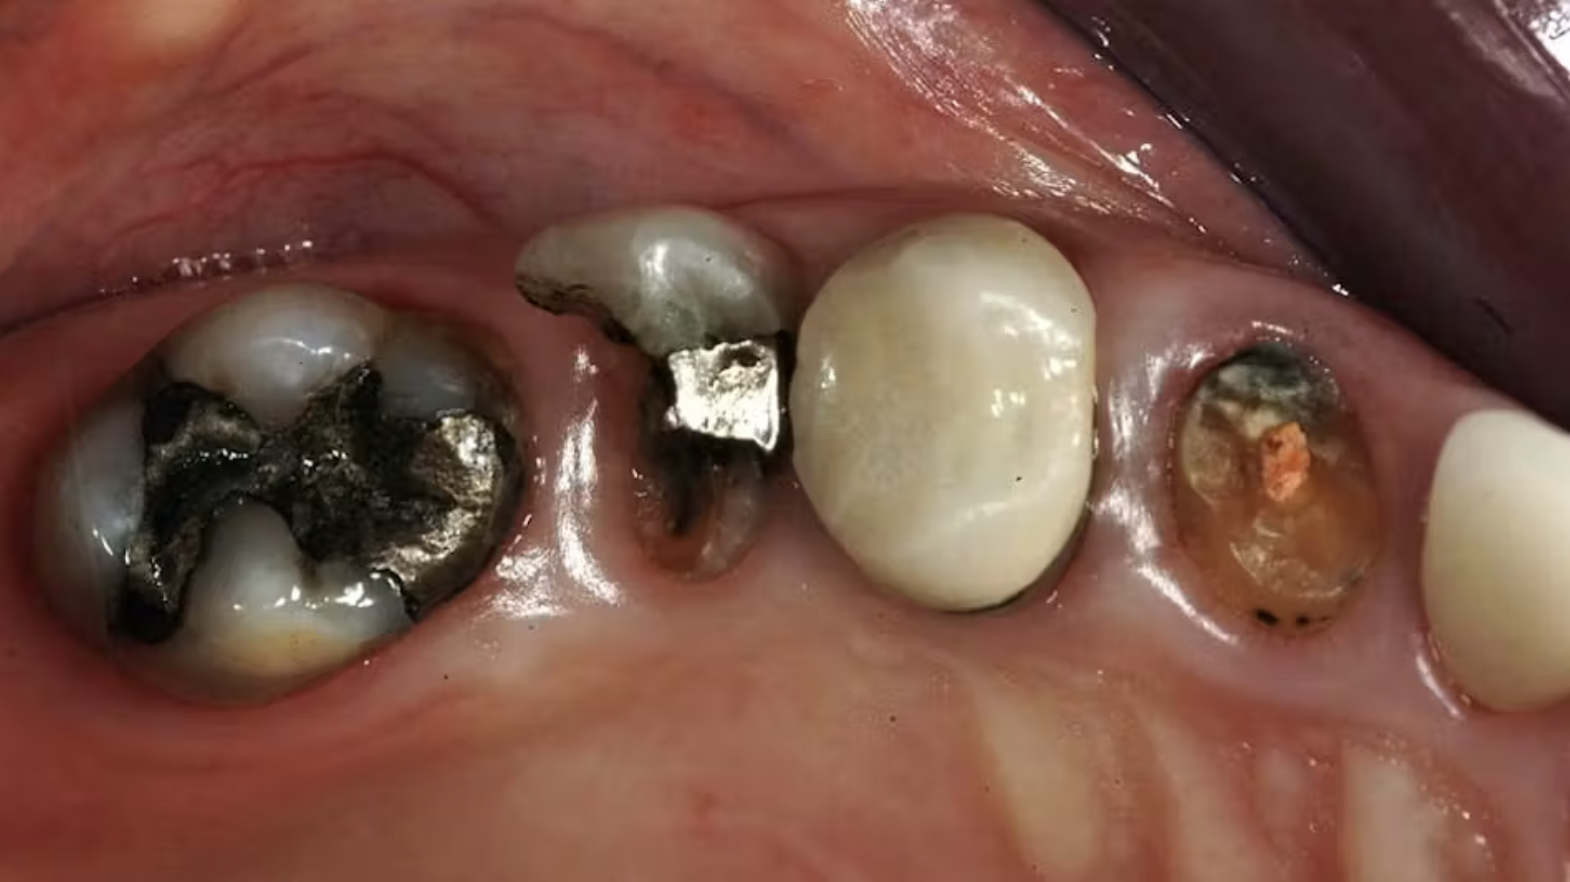

Mô tả ca lâm sàng (Hình 1)

Một góc phần tư hàm với các răng bị phá hủy nặng:

- Răng cối lớn mất hơn một nửa cấu trúc thân răng.

- Răng tiền cối thứ hai không còn khả năng phục hồi.

- Răng tiền cối thứ nhất có thể làm trụ, nhưng cần đánh giá sau khi tháo mão.

- Răng nanh cần điều trị Nội Nha lại và phục hồi bằng chốt – core.

Hình 4:Hình ảnh trước và sau điều trị